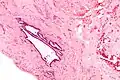

| High magnification micrograph of endosalpingiosis, showing the characteristic cystic spaces lined by a simple epithelium with cilia. H&E stain. | |

It is characterized by cysts with tubal-type epithelium (e.g. ciliated epithelium) surrounded by a fibrous stroma. It is not often associated with hemorrhage.